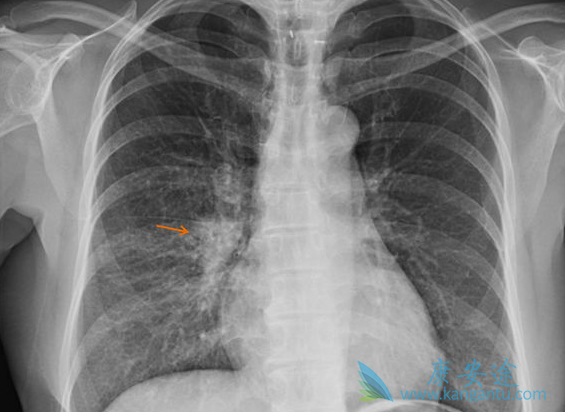

对于 EGFR 突变和 ALK 重排非小细胞肺癌(NSCLC),肺癌脑转移(BM)是诊断和复发时的第二常见部位。25%~50% NSCLC 在整个疾病过程中出现 BM。30%~60% EGFR 突变、40%~70% ALK+ 非小细胞肺癌患者发生 BM。

非小细胞肺癌

BM 影响生存期和生活质量,预期生存期(OS)3~15 个月。因药物很难透过血脑屏障(BBB),放疗是脑转移的治疗基石。对不适合手术或 SRS 的患者,一直以来全脑放疗(WBRT)作为首选。近年来靶向药物如酪氨酸激酶抑制剂(TKIs)对颅内病灶疗效显著,脑脊液(CSF)药物浓度增加。

单发或寡转移考虑局部治疗如 SRS,对 10 个以下脑转移 SRS 是安全的。不适合局部治疗的,保护海马区 WBRT 可减轻神经毒性。靶向治疗透过血脑屏障能力增强,显著改善 NSCLC 脑转移预后。对于驱动基因阳性患者,放疗联合靶向治疗策略可以用于处理颅内转移患者。免疫治疗对于肺癌脑转移有效,脑放疗联合免疫治疗的研究较少。